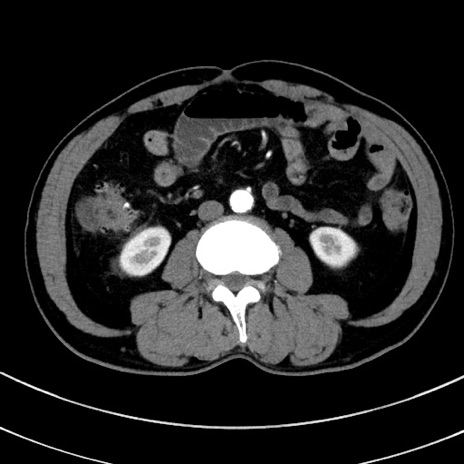

冠状断像

症例8(横断像)

【症例】 60歳代男性

【主訴】 黒色吐物

【現病歴】 4日前から嘔気自覚、2日前の朝食後にも嘔気あり、自分で手で嘔吐反射起こし嘔吐したところ血が混ざっていたため受診。

【既往歴】 5年前汎発性腹膜炎を伴う急性虫垂炎で手術、高血圧、前立腺肥大症、高脂血症

【身体所見】 腹部正中に手術癩痕あり 腹部平坦・軟圧痛なし膨満感あり

【データ】WBC 8400、CRP 4.54